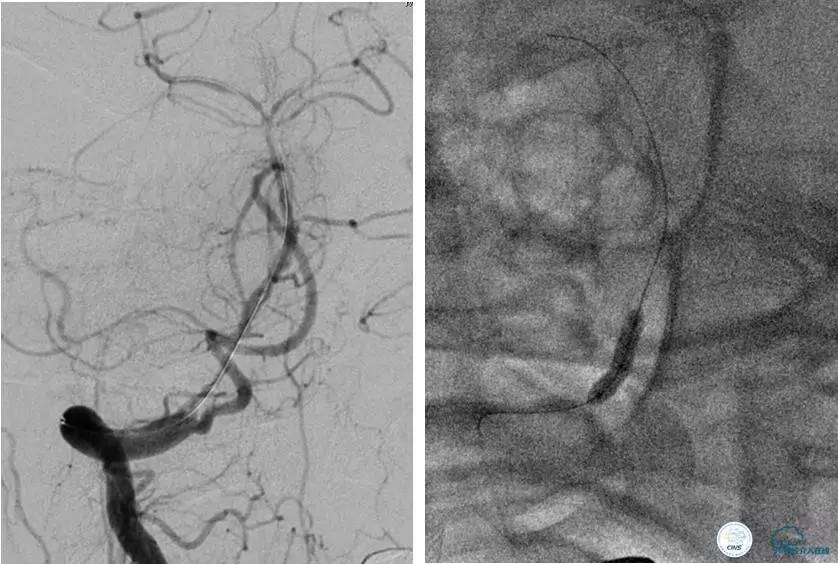

患者:49岁女性,脑梗死30天。

左侧颈内动脉末端闭塞,末端圆钝且有一定成角,开通难度较大,多次尝试导丝才成功穿过闭塞段。

开通效果很满意,术后症状明显恢复。

病例7

患者:反复发作右侧肢体无力、言语不清15天。

导丝很容易通过闭塞段。

顺利置入Wingspan支架,成功开通,手术顺利。